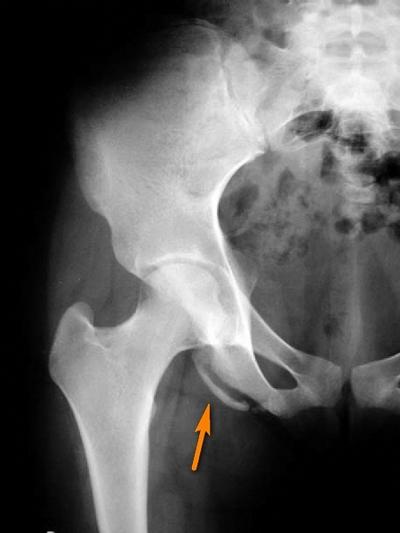

Для исключения переломов необходимо пройти рентгенографию. У взрослых рентген-снимки в большинстве случаев нормальные, за исключением ситуаций, связанных с детскими отрывными переломами или остеохондропатией, которая может развиться из-за длительной нагрузки. У молодежи же рентгенографические исследования часто показывают наличие отрывных переломов.

Основные места возникновения отрывных переломов, от наиболее частых к менее частым, это: седалищный бугор, нижняя и верхняя передние подвздошные ости. Реже наблюдаются переломы гребня подвздошной кости, большого или малого вертела и лобковой кости. У взрослых, как правило, происходят разрывы мягких тканей, которые не фиксируются на рентгенограмме.

Рентгенография: отрывной перелом малого вертела бедренной кости (прикрепление подвздошно-поясничной мышцы)